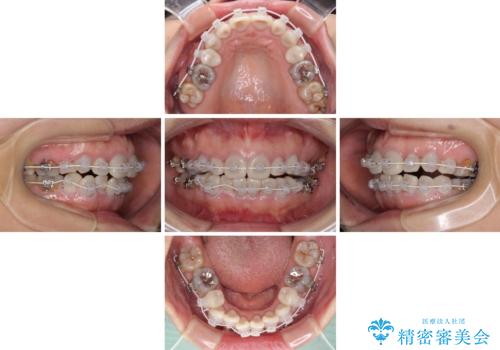

- 小さいころからの歯の変色と矯正治療の後戻りを気にして来院された患者様です。

気になる変色歯を仮歯に変え、その後歯列不正を矯正治療で改善し、最後にオールセラミッククラウンにて補綴治療することとしました。

数十年に及んだ歯の変色が改善されたため、大変満足していただきました。